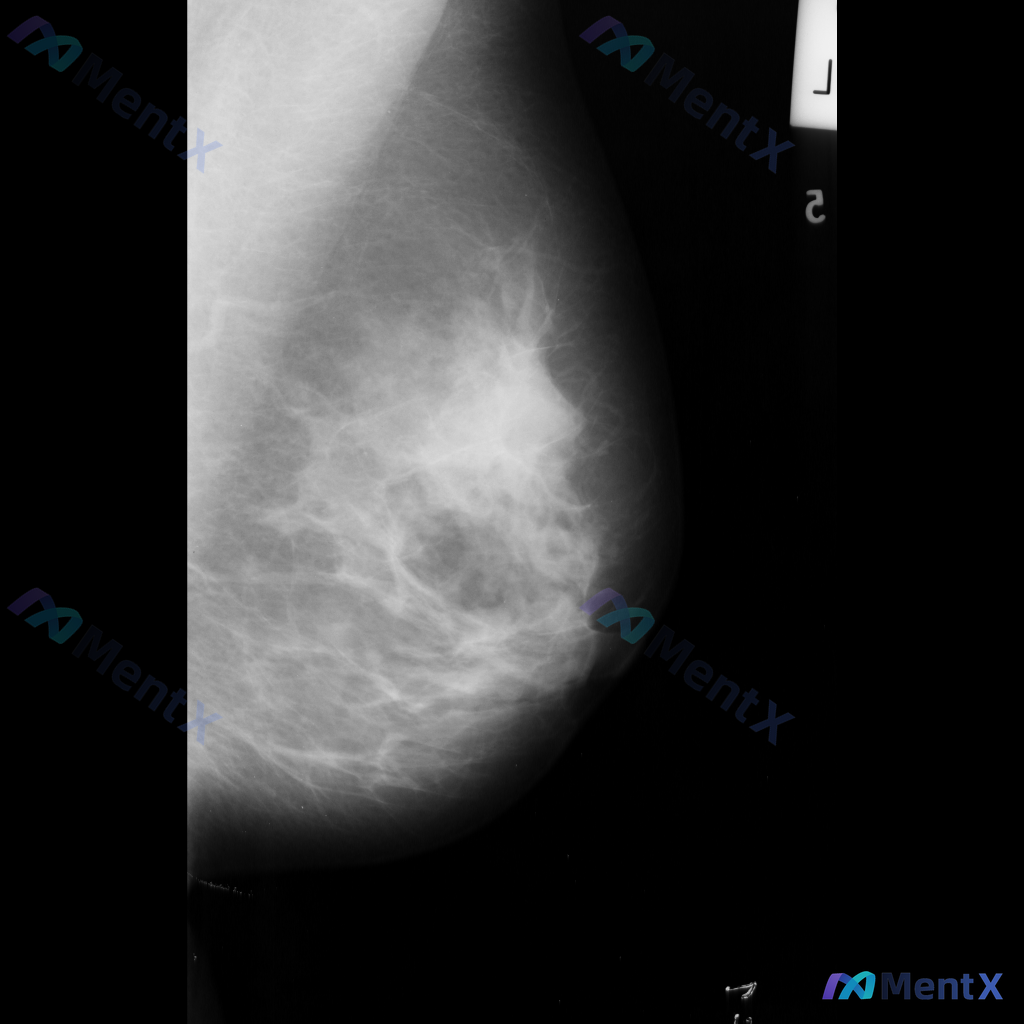

整理到一份乳腺影像学资料的描述: - 主要发现:左乳腺存在局限性异常 - 具体表现:左乳中上象限可见高密度不规则肿块,边缘毛刺状,同时伴有结构扭曲和局部腺体牵拉 目前仅拿到这组影像表现的文字描述,想先跟大家讨论下: 单看这些特征,大家会更倾向于哪种性质的异常?下一步如果要明确诊断,通常会优先安排哪些...

整理到一组乳腺钼靶的影像资料,大家先一起看看: 影像表现: - 病灶位于乳腺上中部(大致外上象限)可见一局限性高密度肿块影 - 形态不规则,边缘有毛刺状改变 - 周围腺体结构有扭曲、牵拉征象 - 肿块内部或附近可见点状钙化,部分呈簇状分布 目前只有这组钼靶表现,大家先不补充更多临床信息的话,大家更倾...